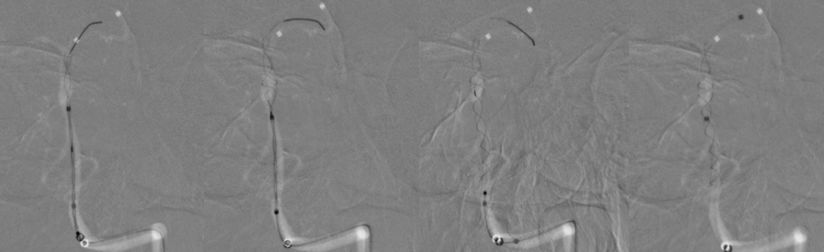

1、患者全身麻醉,右侧股动脉穿刺置入8F动脉鞘,5F中间导管携带6F长鞘超选入左侧椎动脉,行造影及三维旋转寻找最佳工作角度(图8)。

图8

2、调整至合适的工作角度后,撤出5F中间导管,将5F Navien 通过6F长鞘置入左侧V3段。路图引导下由2 m Synchro-14微导丝将T-track支架微导管超选进左侧大脑后动脉P2段(图9)。

图9

3、多个投射角度辅助下,将一枚3x35 mm的Tubridge支架经T-track支架微导管缓慢释放(图10)。

图10

4、支架完全释放后造影可见支架完全覆盖动脉瘤,贴壁良好,载瘤动脉及支架覆盖的双侧AICA及右侧椎动脉通畅(图11)。

图11